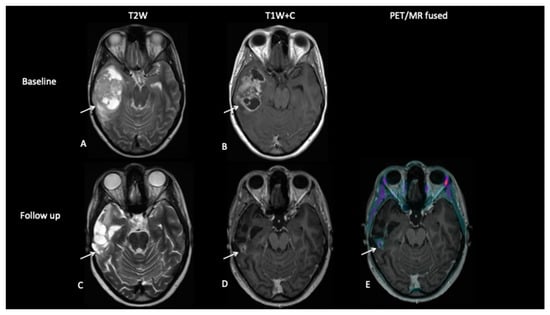

- Patient 2: Early Response Assessment

A 13-year-old female with a large tumour involving left thalamus and basal ganglia, infiltrating into the adjacent white matter, insular cortex and left aspect of the upper brain stem underwent a biopsy of the thalamic component, which confirmed high-grade astrocytoma with a mutation of the variant H3.3 gene. An early response assessment scan 6 weeks after completion of chemoradiotherapy demonstrated no residual enhancement in the tumour, but FDOPA PET showed residual tracer distribution consistent with residual metabolically active disease (Figure 5).

Figure 5.

At baseline, there is non-enhancing tumour involving the left basal ganglia (A,B) with 8F-fluorocholine (FCho) and 18fluoro-L-phenylalanine (FDOPA) avidity (C). Follow-up imaging shows residual non-enhancing tumour (D,E) reported as stable disease, but FDOPA PET demonstrates reduced uptake (F) consistent with metabolic partial response.